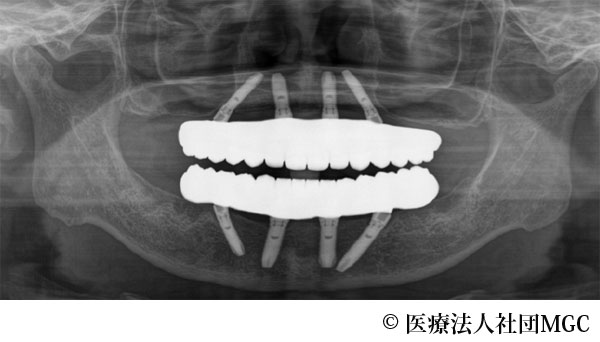

【症例1】上下All-on-4(オールオンフォー)

- 治療後

- 上下All-on-4(オールオンフォー)

- 5,915,800円(税込)

- 8ヵ月

治療法

ご相談の結果、患者様の生活の質(QOL)を向上させ、しっかり噛めるように上下All-on-4(オールオンフォー)を行いました。

治療結果

機能性、審美性ともに改善し、満足していただけました。